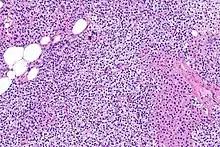

Parathyroid hyperplasia low mag.

Primary hyperplasia of the parathyroid gland, results from both hypocalcaemia and increased phosphate levels by decreasing expression of calcium sensing receptors and vitamin D receptors at the parathyroid gland.[8][4] These decreases in receptor expression lead to hyperfunctioning of the parathyroid. Hyperfunction of the parathyroid gland is thought to exacerbate primary hyperplasia which evolves further to a secondary more aggressive hyperplasia. Histologically, these hyperplasic glands can be either diffuse or nodular.[24] Primary hyperplasia, usually resulting in diffuse polyclonal growth is manly related to reversible secondary hyperparathyroidism. Secondary hyperplasia of the parathyroid gland is more often a nodular, monoclonal growth that sustains secondary hyperparathyroidism and is the catalyst in the progression to tertiary hyperparathyroidism. Nodular hyperplastic glands in tertiary hyperparathyroidism are distinctly larger in both absolute size and weight up to 20-40-fold increases have been reported.[25][26][24]

Parathyroid hyperplasia medium mag.

Parathyroid glands are normally composed of chief cells, adipocytes and scattered oxyphil cells.[27][14] Chief cells are thought to be responsible for the production, storage and secretion of parathyroid hormone. These cells appear light and dark with a prominent Golgi body and endoplasmic reticulum. In electron micrographs, secretory vesicles can be seen in and around the Golgi and at the cell membrane. These cells also contain prominent cytoplasmic adipose.[27][14] Upon onset of hyperplasia these cells are described as having a nodular pattern with enlargement of protein synthesis machinery such as the endoplasmic reticulum and Golgi. Increased secretory vesicles are seen and decreased intercellular fat is characteristic.[27][24] Oxyphil cells also appear hyperplasic however, these cells are much less prominent.

Parathyroid hyperplasia high mag.